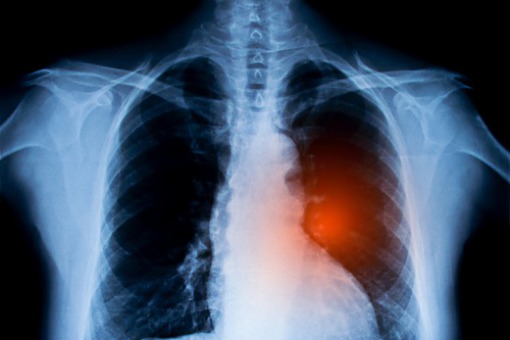

Dwie terapie w niedrobnokomórkowym raku płuca znalazły się w pierwszej piątce listy priorytetów refundacyjnych na rok 2022 (TOP 10 ONKO) opracowanej przez autorytety medyczne. Są one adresowane do pacjentów we wczesnym stadium zaawansowania NDRP i stosowane w ramach leczenia radykalnego.

Rocznie w Polsce na raka płuca zapada 23 tys. osób, a niemal 22 tys. umiera. Wykrywany jest zazwyczaj w późnym stadium zaawansowania, co przekłada się na złe rokowania. Eksperci od wielu lat są zgodni, że w celu poprawienia tych statystyk należy m.in. usprawnić diagnostykę, zapewnić kompleksowość leczenia oraz zwiększyć dostępność pacjentów do nowoczesnych terapii.